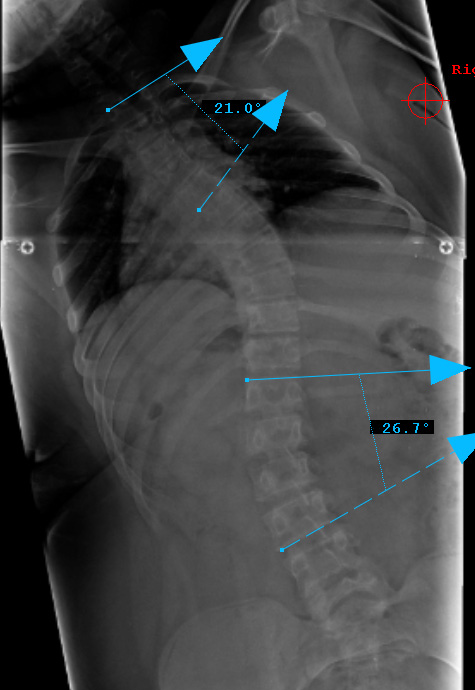

Preop PA View

Preop LAT View